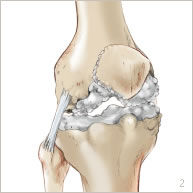

L’arthrose est l’usure du cartilage présent au niveau des surfaces de glissement. Cette usure s’accompagne aussi de remaniements de l’os du fémur, du tibia et de la rotule (figures 2 et 5). Ces modifications occasionnent des douleurs au niveau du genou ainsi qu’un enraidissement et une difficulté à la marche nécessitant l’utilisation importante d’anti-inflammatoires, d’anti-douleurs et parfois même d’une canne.